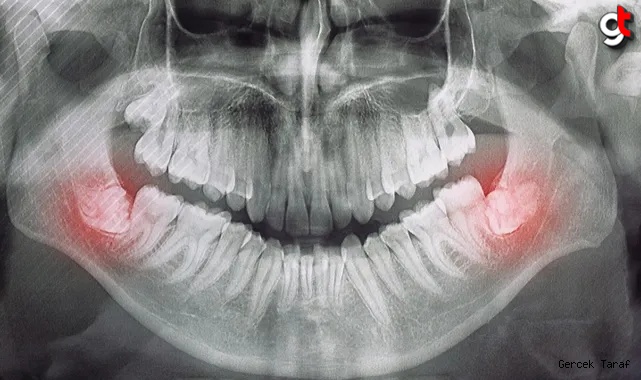

Sıkışma: Yirmilik dişlerle ilgili en yaygın sorunlardan biri, çenede tam olarak çıkmaları için yeterli alan olmadığında ortaya çıkan gömüklüktür. Gömülü yirmi yaş dişleri, çevredeki dişler veya kemik tarafından kısmen veya tamamen engellenebilir. Bu durum ağrı, şişlik ve enfeksiyon gibi çeşitli sorunlara yol açabilir.

Enfeksiyon ve Diş Eti Hastalığı: Kısmen sürmüş yirmi yaş dişleri, yiyecek parçacıklarının ve bakterilerin sıkışabileceği boşluk cepleri oluşturabilir. Bu durum diş eti hastalığının (periodontal hastalık) veya diş enfeksiyonlarının (perikoronit) gelişmesine yol açabilir. Yirmilik dişler sorun yarattığında ağrı yaygın bir semptomdur. Bu ağrı hafif bir rahatsızlıktan şiddetli zonklayıcı ağrıya kadar değişebilir ve kulağa, çeneye veya yüzün diğer kısımlarına yayılabilir.

Kistler ve Tümörler: Nadir durumlarda, kist veya tümör gelişimi gömülü yirmi yaş dişleri ile ilişkili olabilir. Bu büyümeler yakındaki dişlere, kemiklere ve sinirlere zarar verebilir.